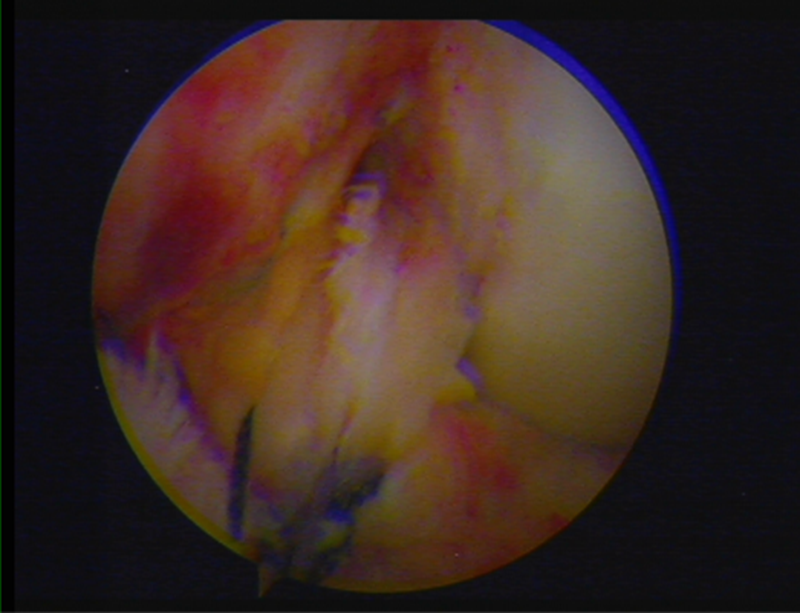

镜下显示ACL残束

内侧半月板

外侧半月板